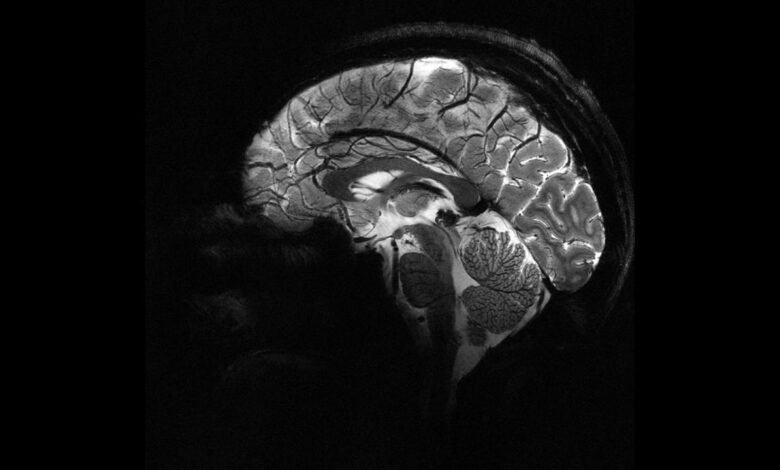

Epilepsiye farklı nedenler yol açsa da, vakaların yaklaşık yüzde 30’u beyindeki yapısal anormalliklerden kaynaklanıyor. Ancak bu lezyonlar, özellikle de beynin kıvrımlarının derinliklerinde saklı olan en küçük olanlar, çoğu zaman MR görüntülerinde fark edilmiyor.

Melbourne Kraliyet Çocuk Hastanesi’nden pediatrik nörolog Emma Macdonald-Laurs liderliğindeki ekip, çocuk beyin görüntüleri üzerinde yapay zekâ modeli eğiterek yaban mersini büyüklüğünde ya da daha küçük lezyonları ortaya çıkarmayı başardı.

Araştırmada kortikal displazi ve fokal epilepsi hastaları üzerinde testler yapıldı. Daha önce MR sonuçları “normal” raporlanan bu çocukların yüzde 80’inde aslında gizli lezyonlar olduğu belirlendi.

Yapay zekâ aracı hem MR hem de PET taramalarını analiz ettiğinde, bir test grubunda yüzde 94, diğerinde yüzde 91 başarı oranı yakaladı. İlk gruptaki 17 çocuktan 12’si beyin lezyonlarının çıkarılması için ameliyat edildi ve 11’i artık nöbetsiz yaşıyor.